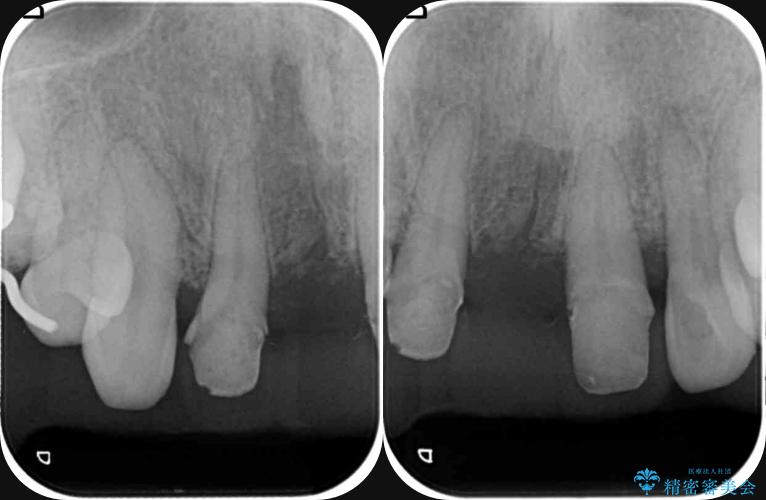

検査の結果、歯周ポケットの測定値は4-6mm程度の値が全顎にわたって認められ、中等度歯周病の状態です。

歯を今後残し、歯周病の状態を改善するため、歯槽骨の再生治療をおこなったのち、歯周ポケットの除去、セラミックブリッジの製作を行う治療計画を実行していきます。

歯周病によって失われた歯を支える骨(歯槽骨)に対し、再生療法を用いることで骨の再生・回復を実現しました。骨の高さが改善されたことで、歯の土台が強化され、将来にわたって歯をしっかりと支え続けられる口腔内環境を整えることができました。